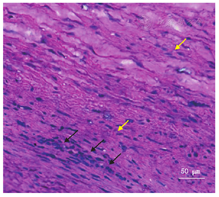

患者男,22岁,主因"突发前胸、后背疼痛2 h"于2019年3月24日入我院血管外科。患者3年前因下腹部剧烈疼痛、突发昏厥于我院就诊,超声提示腹主动脉瘤,腹腔穿刺可穿出不凝血。胸腹主动脉CT血管成像(CT angiography,CTA)提示腹主动脉瘤破裂出血,腹腔积血,腹主动脉直径最大为75 mm(图1A)。患者有吸烟史5年,20支/d,偶有饮酒。家族中其母患马方综合征(Marfan syndrome,MFS),已病故。入院诊断为马方综合征,急诊行"腹主动脉+左侧髂动脉置换术",术后恢复良好出院。今患者于2 h前突发前胸、后背疼痛再次入院。入院体格检查:体型瘦长,四肢、手足细长,蜘蛛指趾,高度近视腹肌紧张,呈板状腹。入院辅助检查:胸腹主动脉CTA(图1B)示:急性主动脉夹层(Stanford A型),破口位于主动脉根部,升主动脉夹层累及整个主动脉弓和降主动脉,主动脉弓部瘤样扩张,且在既往腹主动脉瘤手术部位旁,即肾动脉分支处形成大动脉瘤。超声心动图示:心包腔内可见细线样液性暗区,较厚处约0.4 cm。诊断:急性A型主动脉夹层。急诊行"升主动脉置换+主动脉弓置换+象鼻支架术+腹主动脉置换术"。术后病理(图2):动脉壁标本HE染色显示中膜变性,大量炎细胞浸润,平滑肌细胞增殖,形成较大间隙。术后积极给予输血、补液、抗炎、抑酸、营养心肌等对症支持治疗。但患者终因继发严重感染、多器官功能障碍于2019年3月27日院内死亡。